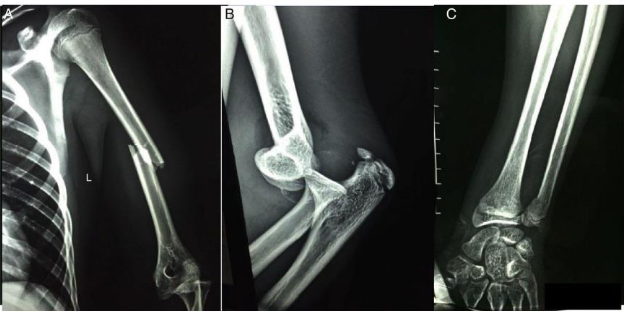

A fratura/ luxação do ombro e do cotovelo necessita da intervenção do ortopedista, sempre o mais breve possível, com redução da fratura (aberta ou fechada), seguida da avaliação da estabilidade articular e do desvio das fraturas. Nos casos crônicos, por falta de condições cirúrgicas ou por negligência, a abordagem cirúrgica, na maioria das vezes, torna-se necessária para redução, estabilização articular e/ou substituição protética. Vários são os exames que podemos realizar de acordo com as condições do paciente.

Tendo como referência as informações do trecho e a imagem acima, é correto afirmar: